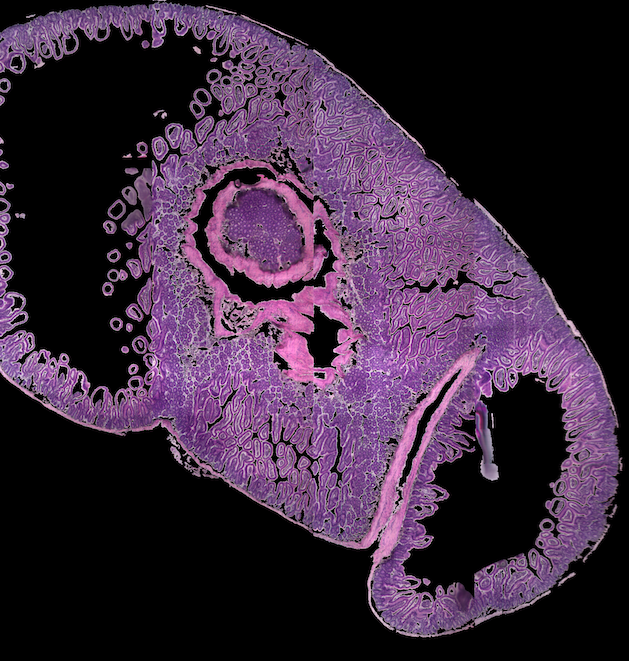

3Scan